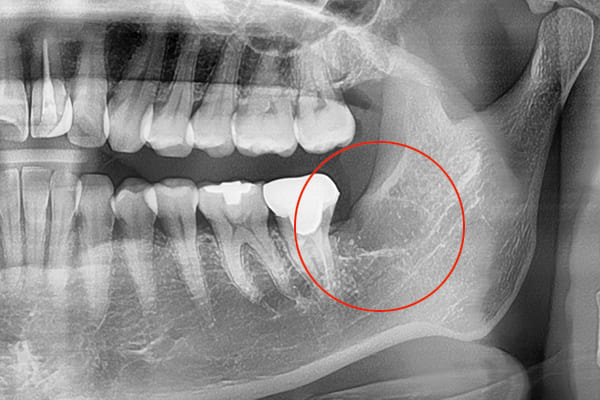

パノラマレントゲンデータ

精密なCTデータで状態把握

親知らず抜歯の症例ケース

親知らずが横向きに生えていて、隣の歯を圧迫している埋伏歯の抜歯ケースです。このタイプは、抜歯が難しい分類になります。

当院では、このような難しい親知らずの抜歯ケースでもなるべく腫れずに、痛くなく抜歯することが可能です。